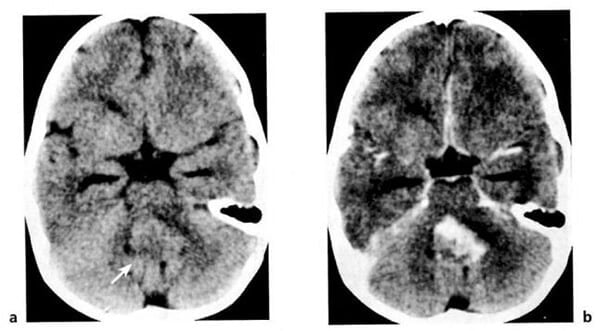

Hình 1.56. U tế bào hình sao độ cao. Trẻ 5 tuổi. Trước tiêm (a), cho thấy u có đóng vôi. U bắt mạnh chất cản quang (b).

Hình 1.58. U nguyên bào tủy của thùy nhộng tiểu não ở trẻ 2 tuổi. Cắt lớp cách sau 10 tháng. Trước tiêm (a), dấu hiệu mơ hồ (mũi tên). Sau tiêm (b), một phần u bắt chất cản quang mạnh.